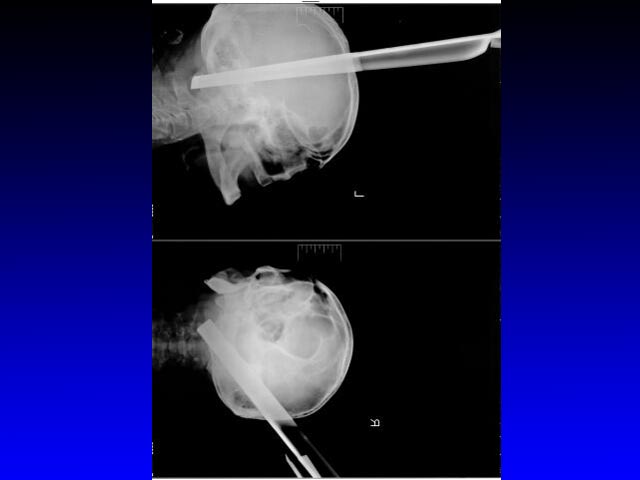

Врачи Красноярской краевой клинической больницы спасли жизнь пациенту с необычной тяжелой травмой. Из головы больного извлекли металлический табурет, одна из ножек которого пробила полость черепа в затылочной области, пройдя на 11 сантиметров до самого его основания сквозь вещество головного мозга, сообщает сайт министерства здравоохранения края.

Службой скорой помощи мужчина был доставлен в приемный покой. Оттуда его в экстренном порядке перевели в операционную. Дежурная бригада нейрохирургов извлекла инородное тело. По словам медиков, операция прошла без осложнений: несмотря на удаление столь массивного предмета, у больного даже не возникло ожидаемого кровотечения.